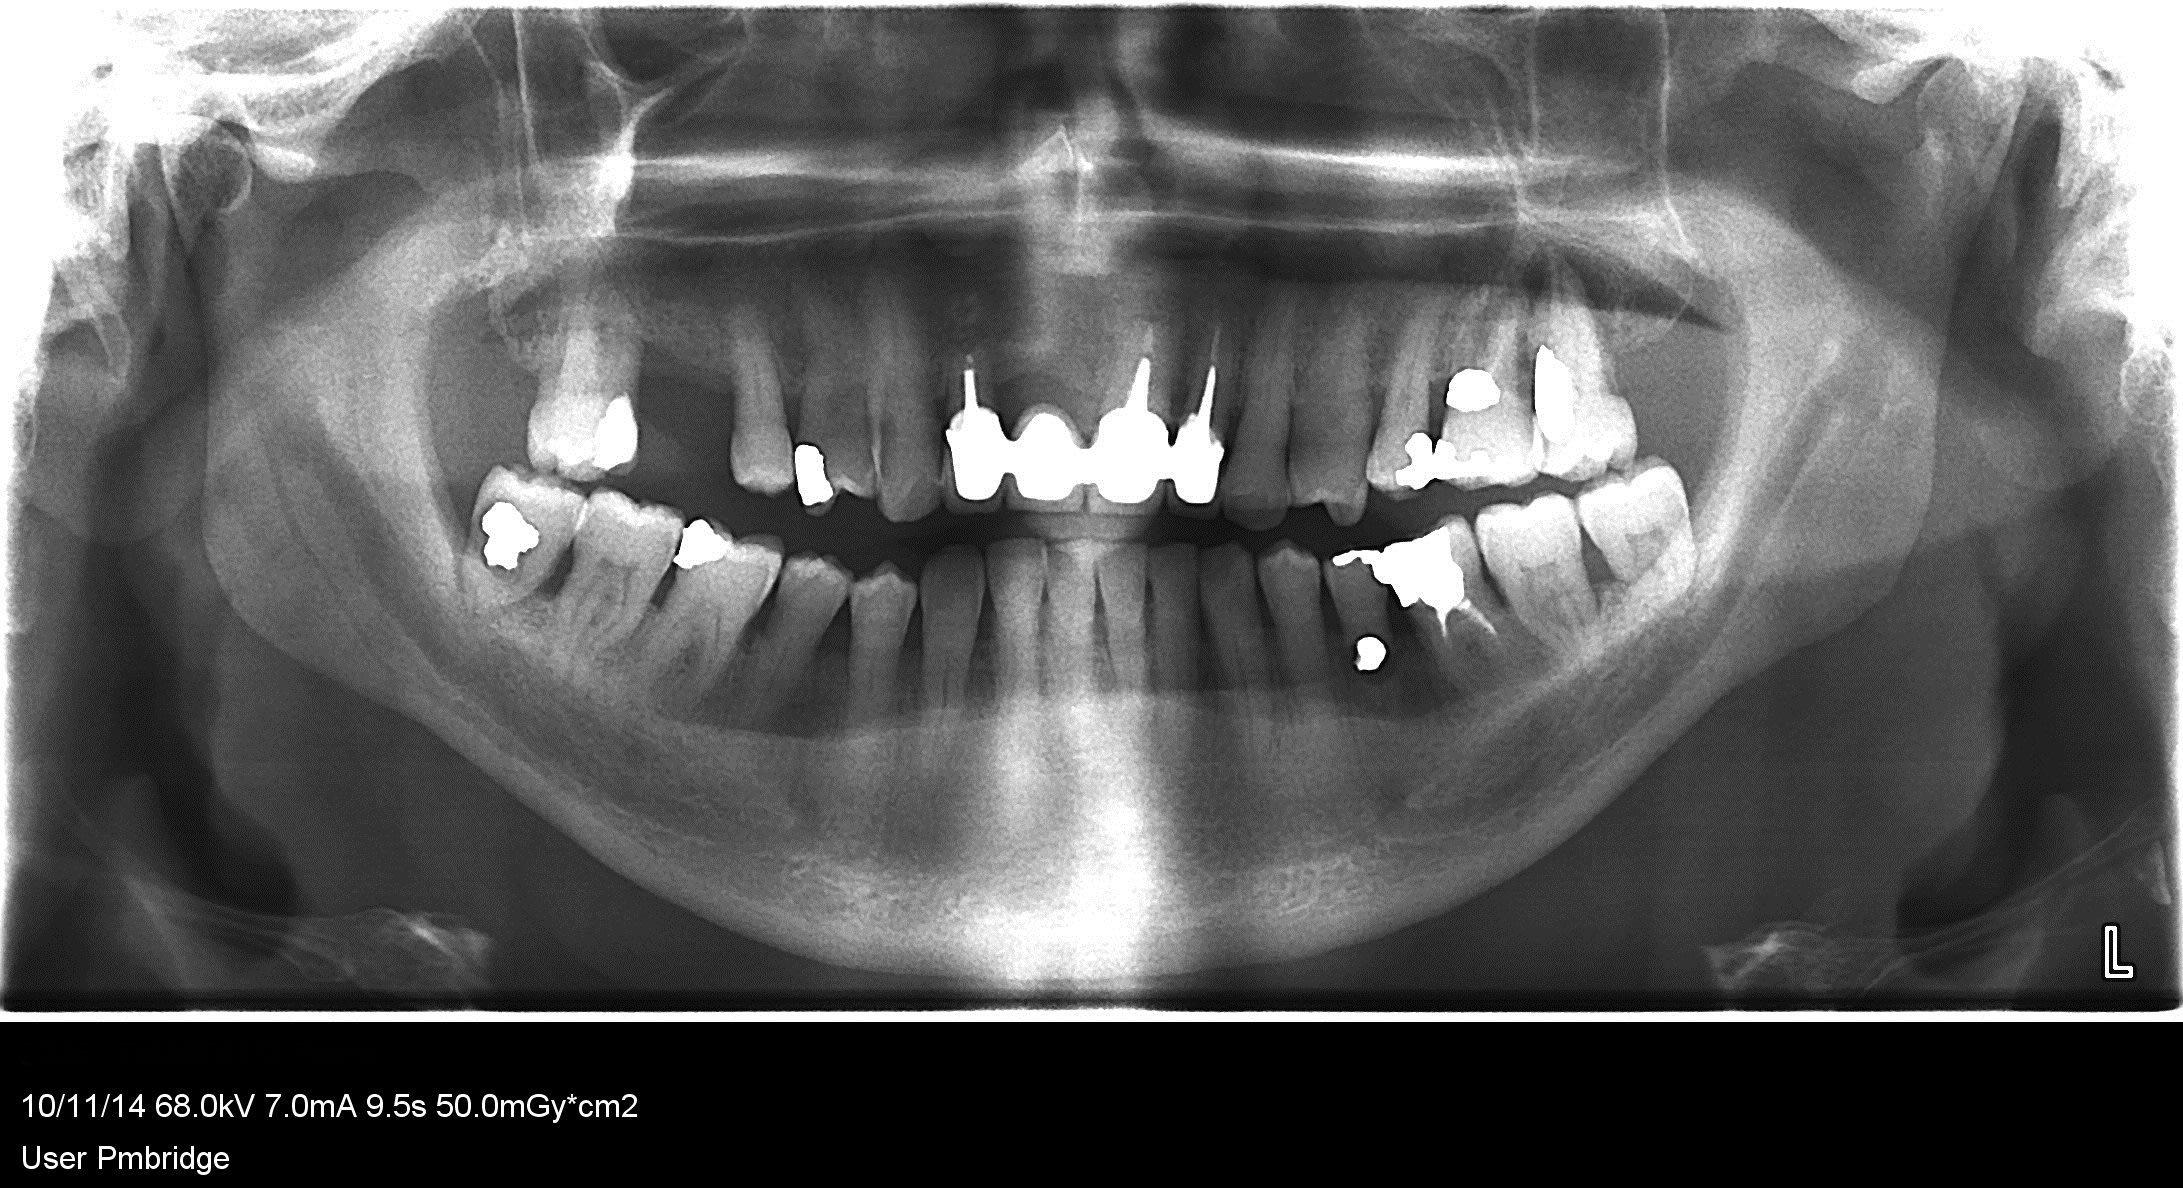

chichi

autres radios